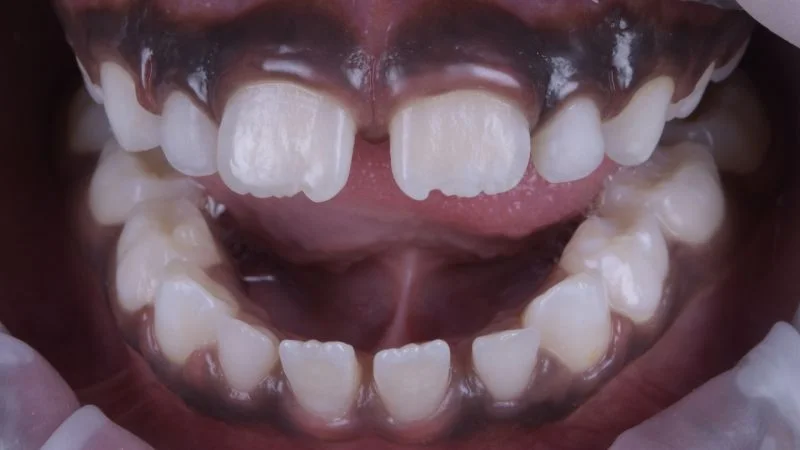

Behandlungsergebnis.

Ansicht des Zahnes 11 von lateral.